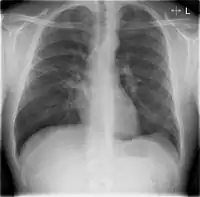

Chest X-rays and X-ray computed tomography (CT) can reveal areas of opacity (seen as white), indicating consolidation.[13] CAP does not always appear on x-rays, sometimes because the disease is in its initial stages or involves a part of the lung not clearly visible on x-ray. In some cases, chest CT can reveal pneumonia not seen on x-rays. However, congestive heart failure or other types of lung damage can mimic CAP on x-ray.[15]

When signs of pneumonia are discovered during evaluation, chest X-rays and examination of the blood and sputum for infectious microorganisms may be done to support a diagnosis of CAP. The diagnostic tools employed will depend on the severity of illness, local practices and concern about complications of the infection. All patients with CAP should have their blood oxygen monitored with pulse oximetry. In some cases, arterial blood gas analysis may be required to determine the amount of oxygen in the blood. A complete blood count (CBC) may reveal extra white blood cells, indicating infection.

X-ray findings indicating hospitalization include:

- Involvement of more than one lobe of the lung

- Presence of a cavity

- Pleural effusion